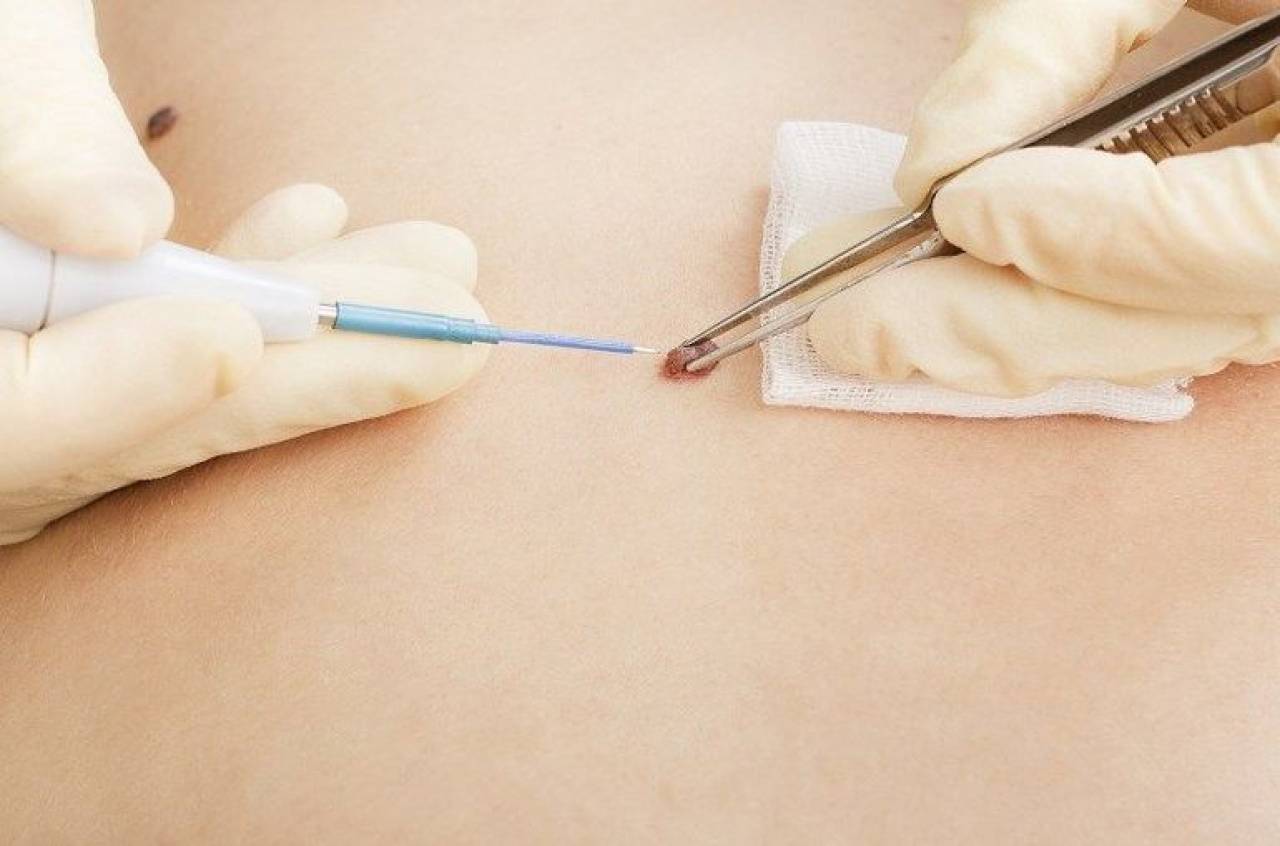

Фото: метод криодеструкции

- Радиоволновое удаление. Это хирургическая техника, в основе которой лежит разрушение клеток под воздействием волны. Процесс длится около 5-10 минут. После операции в большинстве случаев не наблюдается осложнений. Для удаления папиллом в чувствительных местах перед радиоволновым методом проводится анестезия.

- Криотерапия. Нарост прижигают жидким азотом. Пациент ощущает легкое жжение и холод. Через некоторое время после процедуры папиллома отпадает. Преимущество метода заключается в его безболезненности, а также в отсутствии рубцов после удаления.

- Электрокоагуляция. В основе лежит использование электрического высокочастотного тока. На поверхность папилломы и участка вокруг нее накладывается проводящий электрод. Далее пораженное место обрабатывают диатермическим ножом, в результате чего происходит мощное выделение теплоэнергии, и сосуды разрушаются. Процедура проходит быстро и безболезненно, а ранка заживает через несколько дней.

- Хирургический метод. Это один из консервативных способов удаления, утративший сегодня популярность. Однако, чтобы избавиться от внутрипротоковой папилломы молочной железы, подойдет именно этот метод.